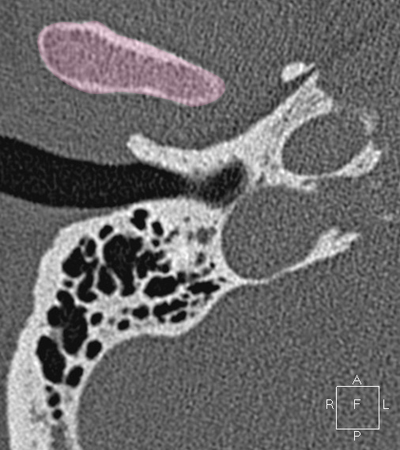

Sigmoid sinus Jugula bulb Horizontal petrous carotid Groove for tympanic (Jacobson's) nerve Facial nerve (f3), mastoid segment Anterious wall of bony EAC (tympanic bone) Mandibular condyle